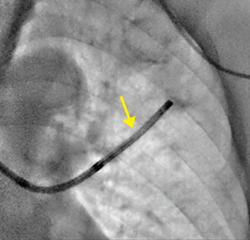

症例2 新画像処理条件の透視像。気管支鏡内のEBUSの先端の位置も明瞭に見える(↓)。